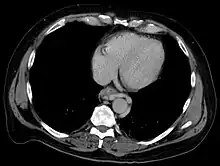

Axial CT showing esophageal varices in liver cirrhosis with portal hypertension

Dilated submucosal veins are the most prominent histologic feature of esophageal varices. The expansion of the submucosa leads to elevation of the mucosa above the surrounding tissue, which is apparent during endoscopy and is a key diagnostic feature. Evidence of recent variceal hemorrhage includes necrosis and ulceration of the mucosa. Evidence of past variceal hemorrhage includes inflammation and venous thrombosis.